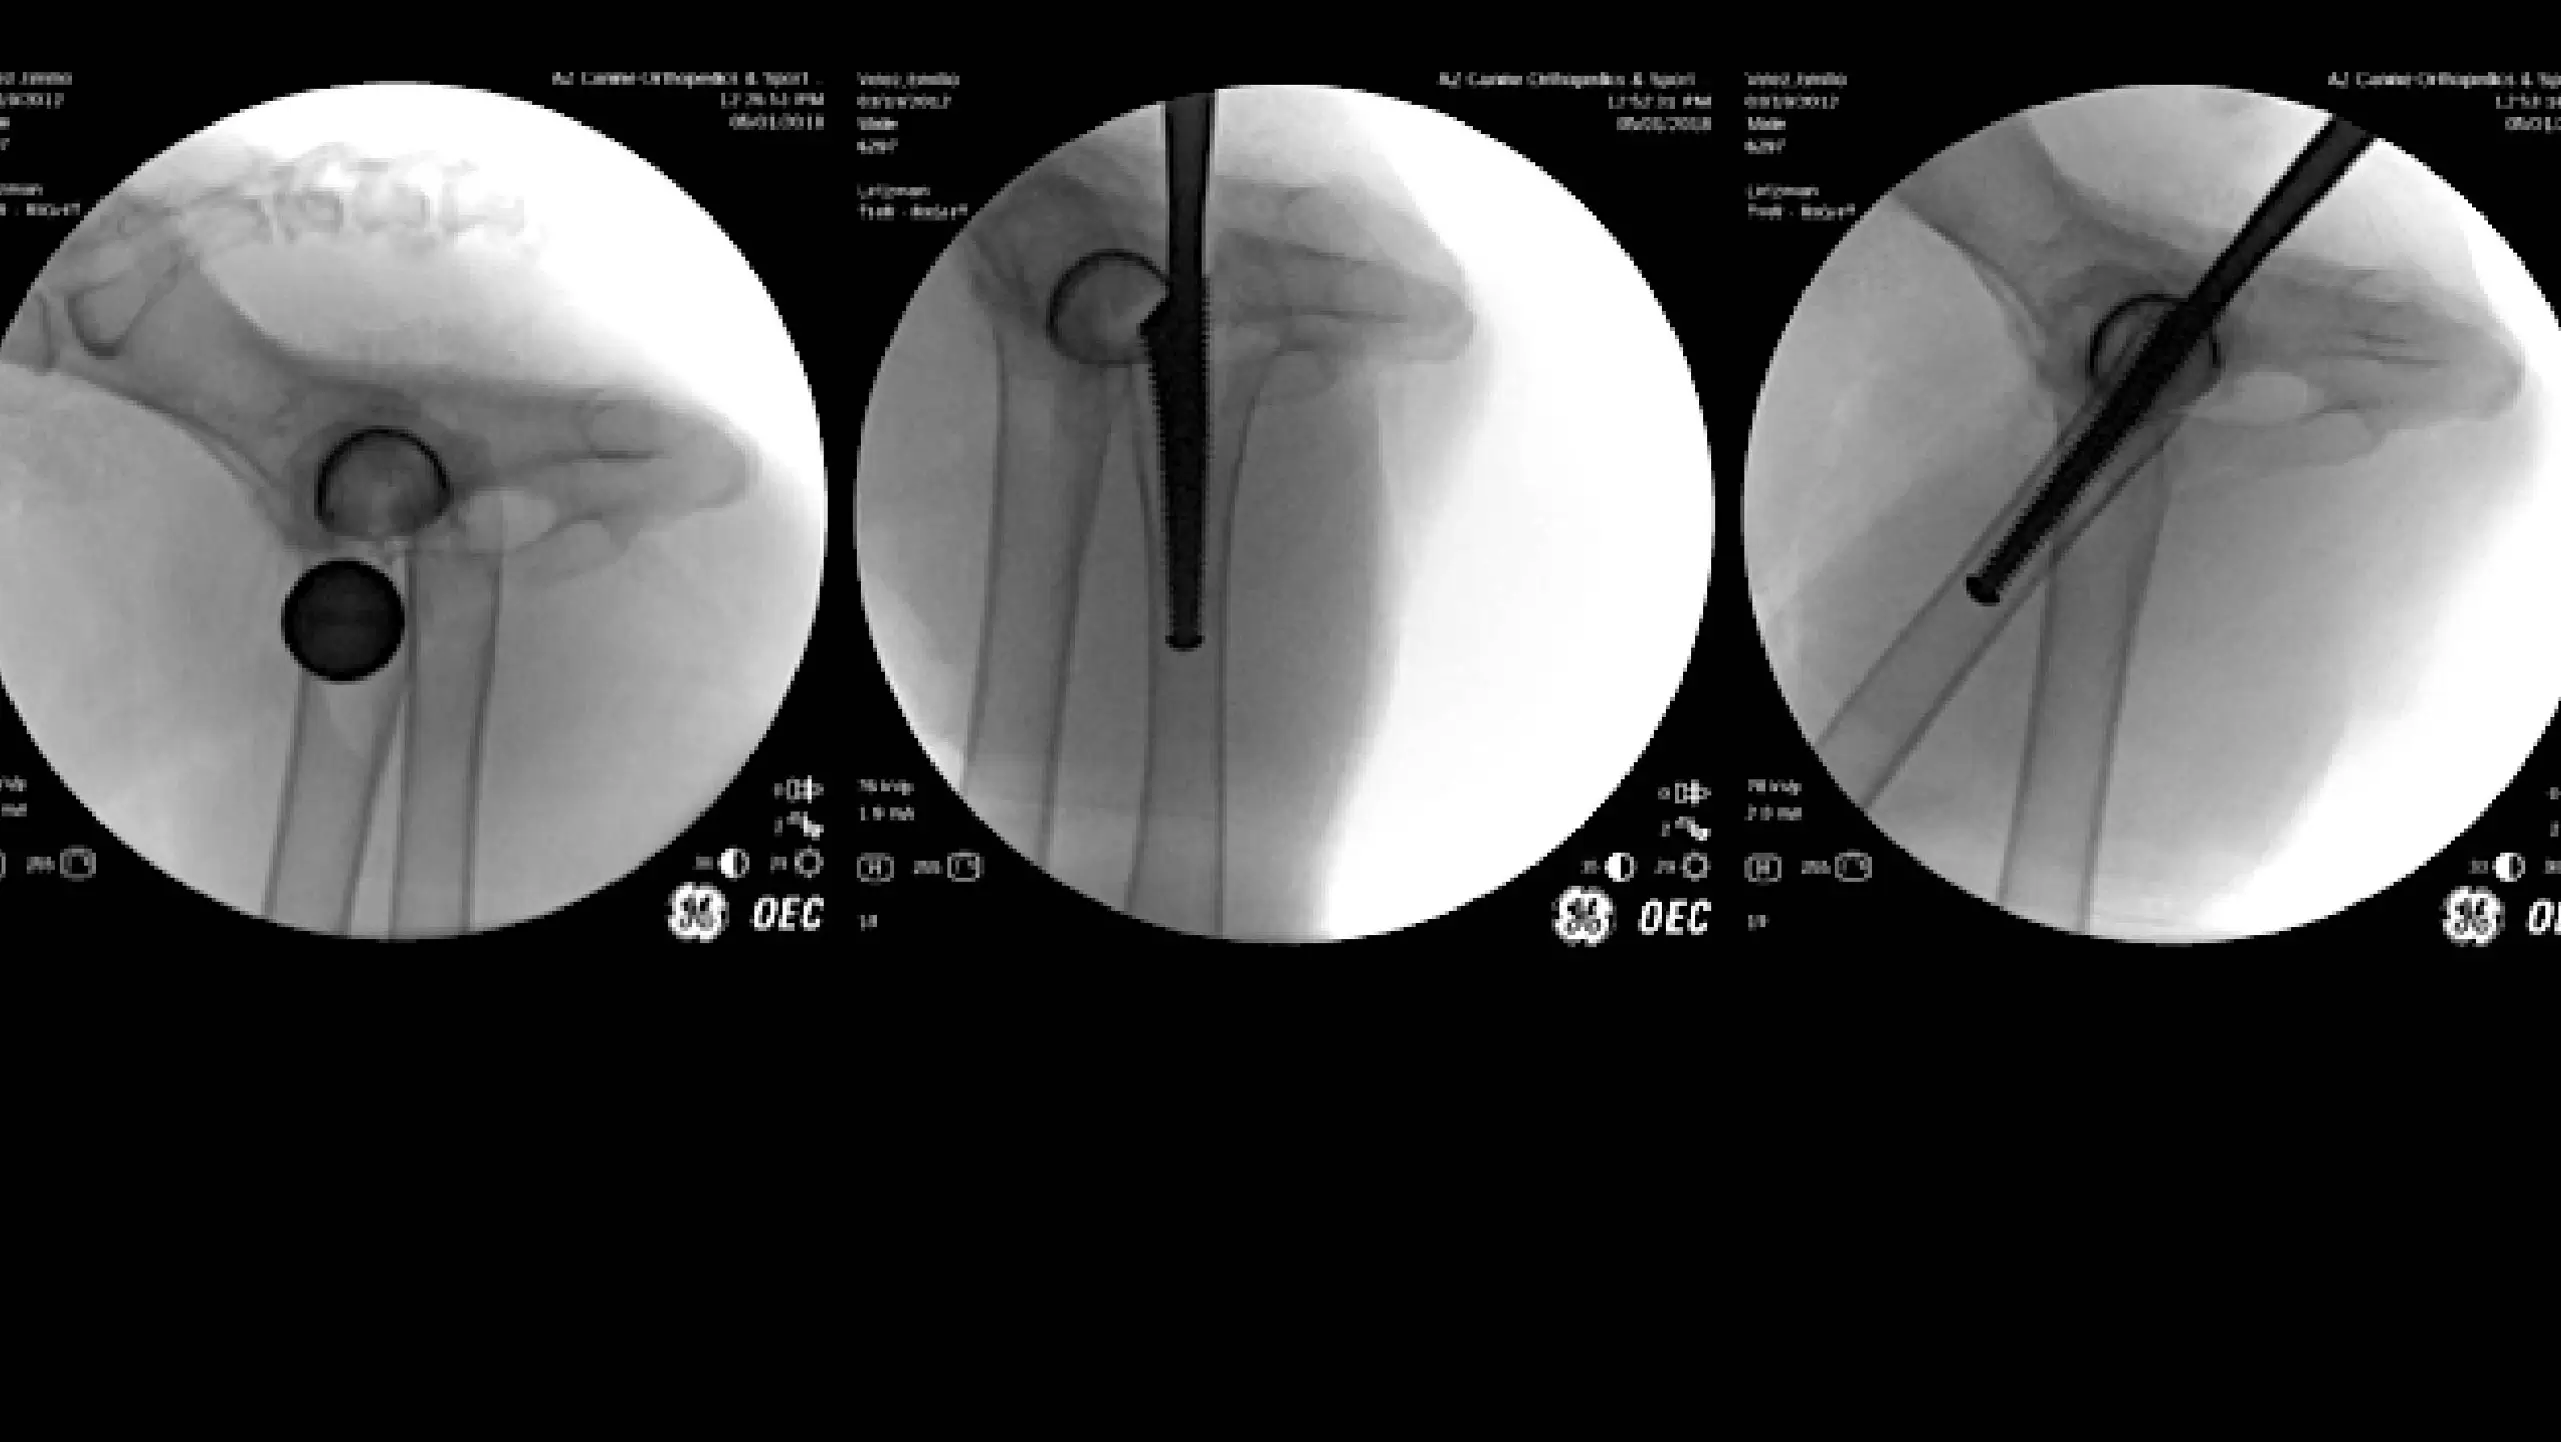

CrCL Tear (TPLO)

Orthopedic Trauma & Minimally Invasive Fracture Repair

Second Look Arthroscopic Findings After Tibial Plateau Leveling Osteotomy